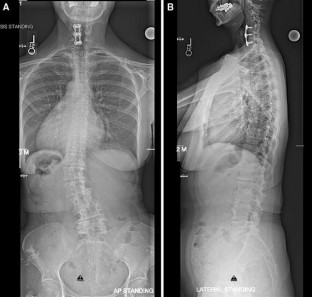

Sacropelvic fixation should be considered in any patient with a long construct ending in the sacrum, those patients with associated risk factors for loss of distal fixation or high risk for pseudarthrosis at L5–S1, and those undergoing three column osteotomies or vertebral body resections in the low lumbar spine. Current pelvic fixation techniques with iliac screws, multiple screw/rod constructs, and S2-alar-iliac screws are all viable techniques for achieving pelvic fixation.

There is growing evidence that pelvic fixation may become the standard for obtaining long fusions in adult scoliosis. Although technically challenging, in selected cases the use of four pelvic screws and/or four rods across the lumbosacral pelvis can help address pseudarthroses, implant breakage, and screw pullout secondary to osteoporosis. Ultimately, indications and techniques should be individualized to the patient and based on surgeon preference and experience.